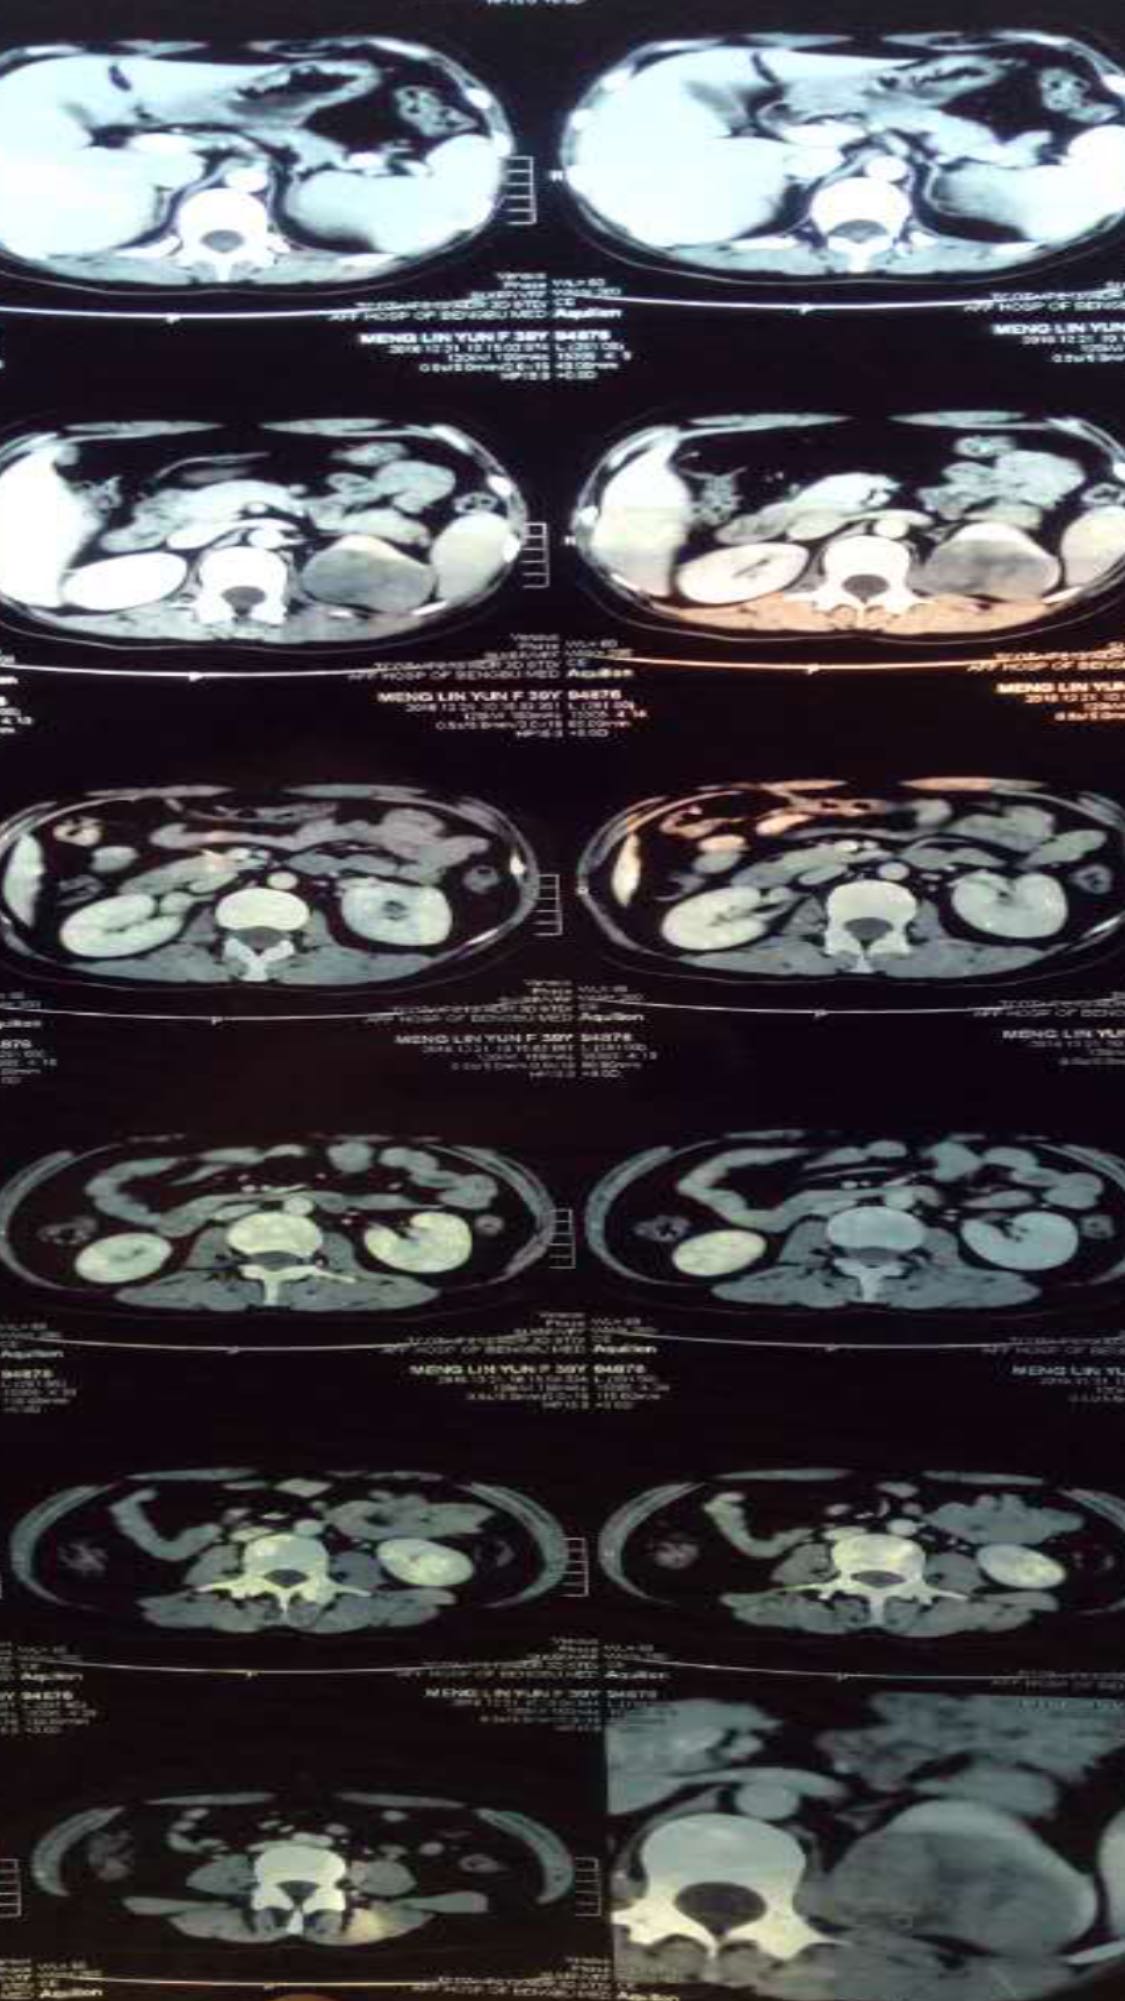

肾透明细胞肉瘤

肾细胞癌

主诉 病史

左腰部疼痛不适5天

左肾透明细胞肉瘤,进行了左肾根治性切除术

肾透明细胞肉瘤是比较罕见的肾恶性肿瘤,具有高度的侵袭性和复发性,术后常进行化疗放疗等